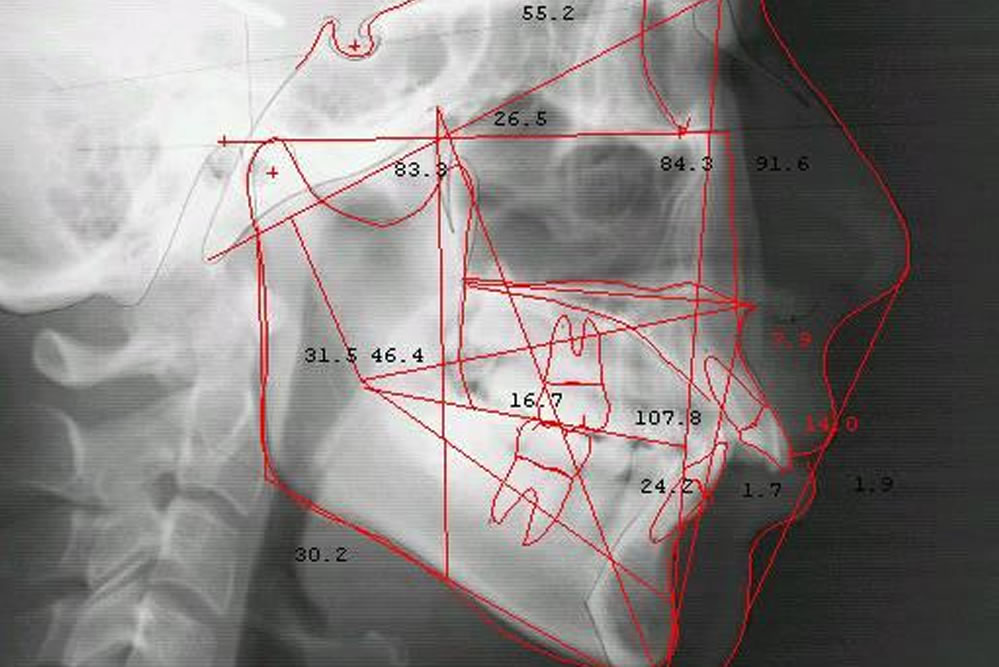

セファロレントゲン

顎から頭部までのX線規格写真(セファログラム)が撮影できる特殊なレントゲンです。顎をはじめ、顔面や頭部までを総合的に分析し、適切な診断を致します。